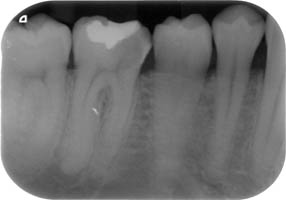

La endodòncia és la part de la odontologia que tracta la pulpa dental (o nervi de les dents). Aquesta pulpa està localitzada en un sistema de conductes radiculars que tenen les dents.

La majoria de vegades, les patologies que afecten la pulpa dental són produides per grans càries. Quan això succeeix, es produeix una inflamació o necrosis del teixit de la pulpa dental, i és necessària la extirpació d'aquesta. Això requereix un desbridament i conformació d'aquests conductes, i una obturació o segell dels mateixos amb materials biocompatibles. Això és el que es coneix com una endodòncia, o vulgarment dit, "matar el nervi".

Aquest tractaments és complexe. Normalment, es pot realitzar en una visita, tot i que de vegades es necessitin més segons la complexitat del cas (nombre d'arrels del queixal, corvatura i longitut, de les mateixes, calcificacions de la pulpa, etc.)